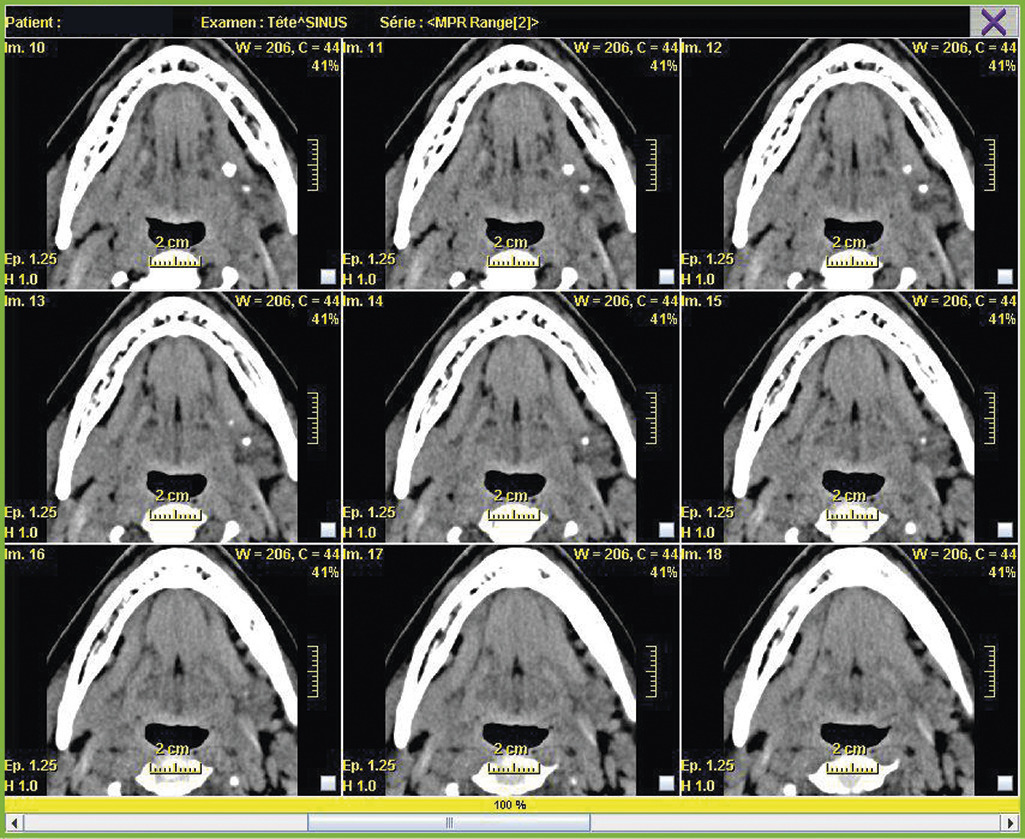

Le cone beam

Cette tomographie volumique par faisceau conique est une technique de tomodensitométrie permettant de produire une radiographie numérisée. Cet examen peut remplacer le scanner car il est moins irradiant, moins coûteux, et présente moins d’artéfacts dentaires ; en revanche, il n’est pas pris en charge par l’Assurance maladie dans cette indication et montre mal les tissus mous (fig. 10).